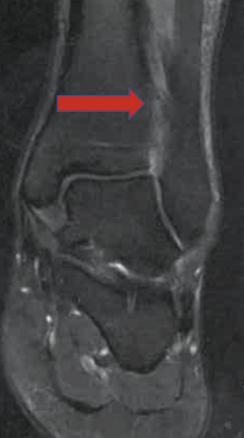

À J15, une gêne fonctionnelle importante liée à la douleur à l’appui et une sensation d’instabilité persistent. L’inspection ne met pas en évidence d’hématome mais un discret épanchement tibio-talien. La mise en compression de la syndesmose (« test de Hopkinson » ou squeeze test ; fig. 1) déclenche une franche douleur remontant le long de la face antérieure du tiers inférieur de la jambe. Il n’existe, en revanche, pas de douleur à la palpation de l’insertion talienne du ligament tibiofibulaire antérieur (LTFA).